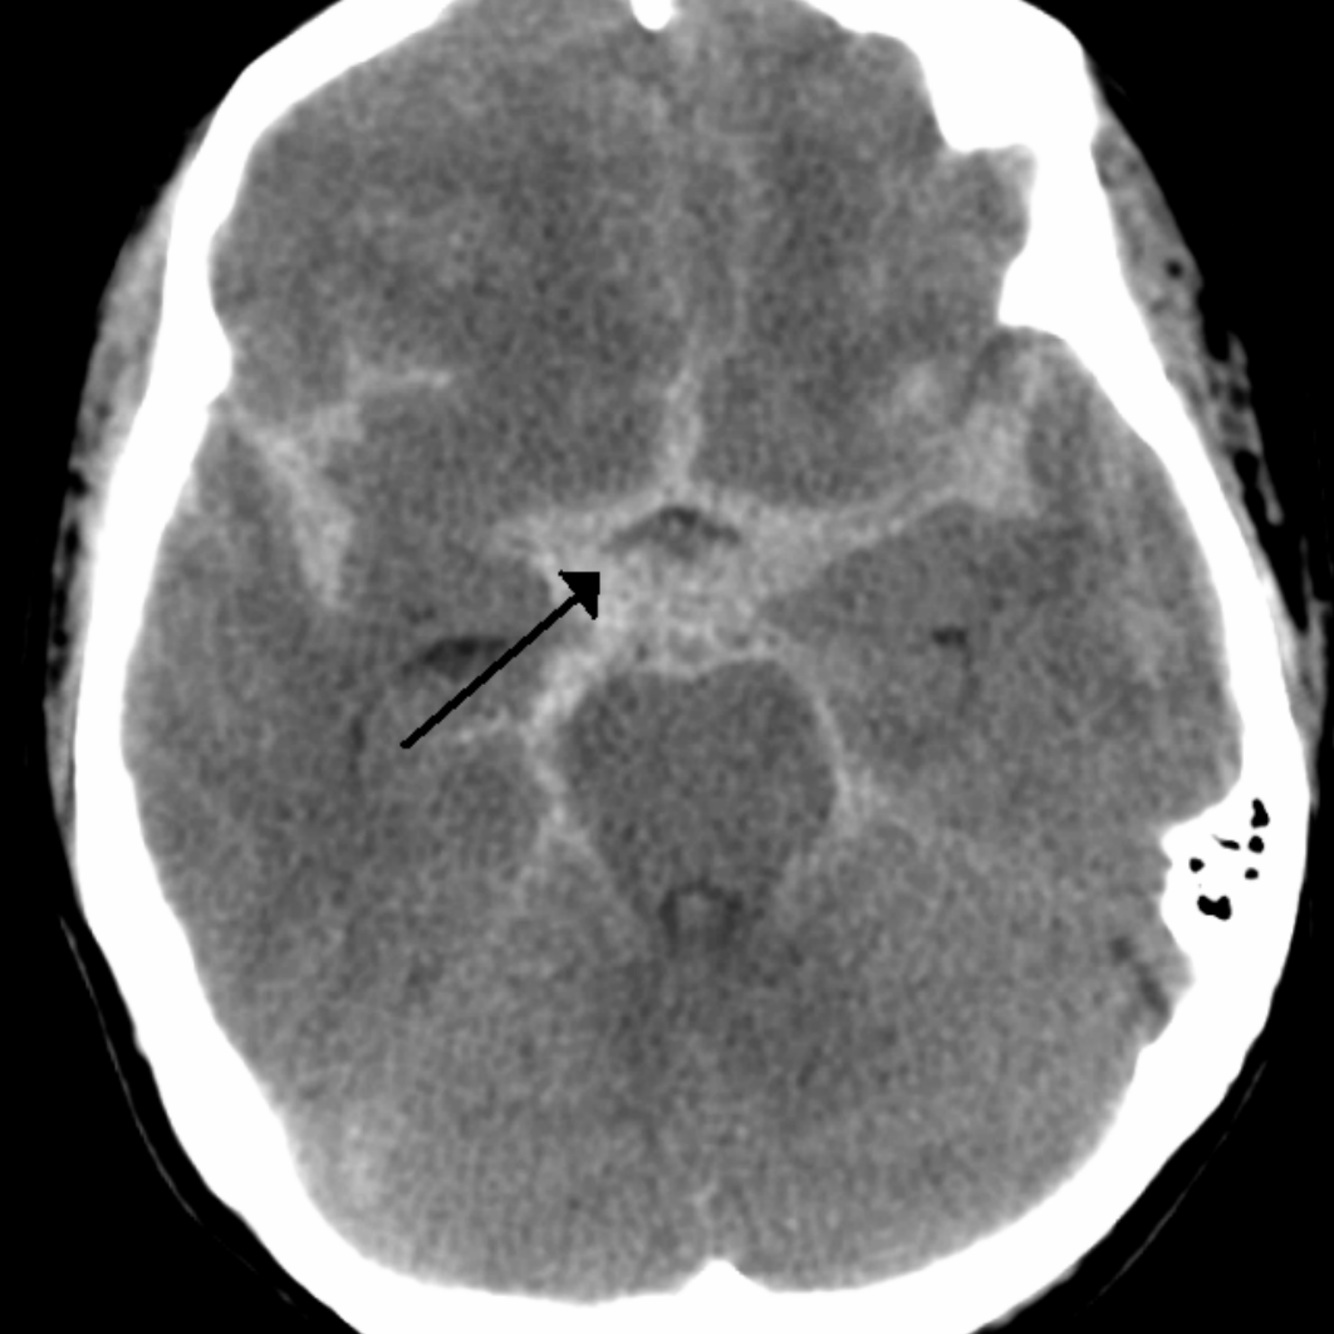

13

A

Extradural haemorrhage

Haematoma expansion limited by sutures of the skull so expands towards the brain giving characteristic biconvex hyper dense area

Anattomical invovlement extradural haemorrhage

Extradural haemorrhage is usually caused by rupture of the middle meningeal artery in the temporo-parietal region. It can be associated with a fracture of the temporal bone. It occurs between the skull and dura mater. On a CT scan they have a bi-convex shape and are limited by the cranial sutures (they can’t cross over the sutures).